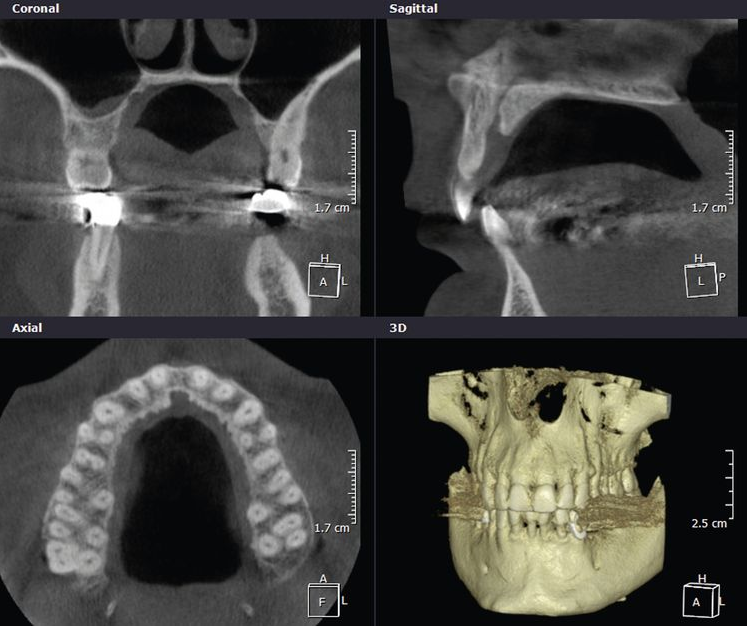

Abb. 1: Die Daten können in verschiedenen Ebenen wiedergegeben werden.

Das Grundgerüst der fertig rekonstruierten Datensätze sind die Voxel (engl.: volumetric element). Sie stellen zugleich die kleinste Baueinheit dar und sind bei der DVT in aller Regel isotrop, also würfelförmig. Die CT hingegen liefert oftmals – abhängig von der selektierten Schichtdicke – anisotrope Voxel. Durch weitere Rechenprozesse können die Daten auf verschiedenste Weise dargestellt werden. Die multiplanaren Rekonstruktionen stellen die sinnigste Weiterverarbeitung der Daten dar. Hierbei wird das Volumen durch senkrecht zueinander stehende Ebenen zerlegt, wodurch die Ansichten Axial, Sagittal und Koronal erzeugt werden (Abb. 1 a, b, c) . Die Komposition dieser drei Ebenen ergibt ergänzt durch den vorgang des Renderings dreidimensionale Modelle (Abb. 1d)